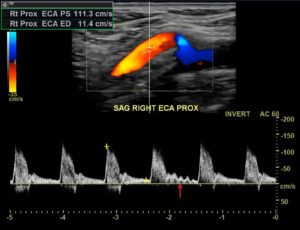

There is another trick we have to identify the external carotid artery. It is called the temporal tap. The sonographer taps gently on the patient’s superficial temporal artery while imaging the external carotid artery. Because the superficial temporal artery is connected to the external carotid artery, the tapping will appear on the ultrasound:

One word of caution, though. If you tap hard enough over someone’s forehead, any tapping will appear on the waveforms 😉